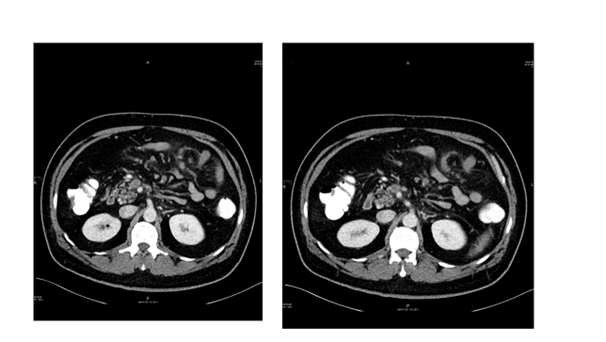

50-year-old gentleman previously healthy, non smoker, non alcoholic presents to Emergency Department (ED) with left hypochondrial colicky non radiating pain, aggravated by heavy meal for five days, and associated with severe diaphoresis and nausea. He sought for medical advice twice and treated first time as a case of gastritis, and on second visit basic blood work including CBC, U&E, Lactate, LFTs were within normal range and Ultrasound showed no abnormalities, and discharged on Paracetamol and antacids. Patient did not improve inspite of compliance with the prescribed medications and presented to our ED by the same complaints, on examination, patient was stable vitally, with soft non-tender abdomen and normal bowel sounds. He underwent comprehensive study including Ct abdomen with contrast which reveled: Thrombosis of the superior mesenteric vein and its branches noted. The thrombus is seen extending, through the main portal vein partially occluding its lumen, to involve the splenic vein and right portal vein as well (Figure 2). Enoxaparin was started for him, work up for thrombophilia was sent, GI consultation was made to arrange for OGD (Oesophago–gastro-Dudenoscopy), looking for malignancy which revealed erosive gastritis with significant modularity, CLO test was negative, tumor markers were sent (CA 125- CA19-9 CEA) were normal, homocysteine 13.9 (high), B12=111 (low), during his stay at hospital patient has no complain, and his physical exam was normal.

Patient discharged from hospital with diagnosis of homocystienemia, B12 deficiency, and normal thrombophilia work up. With plan to start rivaroxiban 20mg PO OD, frequent follow-up at clinic. After 6 month ct abdomen with contrast repeated and revealed recanalization of the portal vein and splenic vein with partially recanalization of the superior mesenteric vein which is surrounded with fat standing and multiple sub centimeter of lymph nodes.